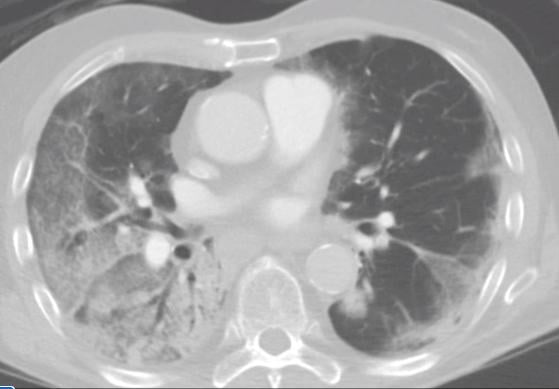

This photo gallery shows the variety of radiological presentations of COVID-19 (SARS-CoV-2) in medical imaging, including computed tomography (CT), radiograph X-rays, ultrasound, echocardiograms and magnetic resonance imaging (MRI). The radiology images show examples of typical COVID pneumonia in the lungs and the numerous complications the virus causes in the body in multiple organs, including the brain, kidneys, heart, abdomen and vascular system.

Ultrasound, especially hand-held ultrasound imaging devices, have become a primary imaging modality for novel coronavirus because of the ease to bag the device and sterilize it after use. CT and mobile X-ray systems are also used as front-line imaging systems for COVID-positive or suspected COVID patients.